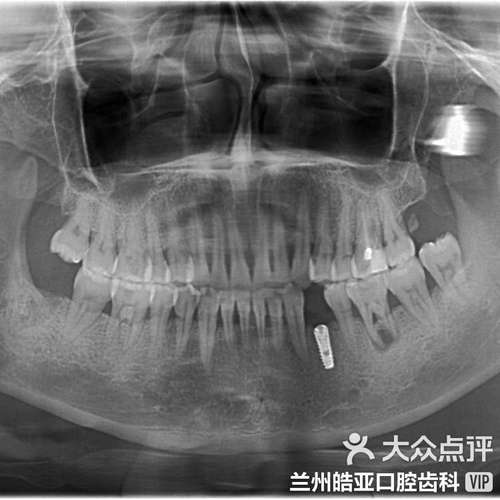

愈合与骨结合期(通常3-6个月):

- 软组织愈合: 切口愈合,牙龈组织逐渐覆盖种植体顶部(如果采用埋入式愈合),牙龈沟开始尝试在种植体周围形成新的附着。

- 骨结合: 种植体表面与周围牙槽骨发生直接的骨性结合,这是种植体成功的基础。

- 牙龈沟形态重建: 在此期间,牙龈组织会努力适应种植体这个“异物”,试图在种植体表面形成类似天然牙的袖口结构,这个过程是动态的,最终形态取决于多种因素(见下文影响因素)。

种植体和基台设计:

- 基台外形: 锥形、光滑的基台边缘有助于形成更健康的袖口,平台转移设计(基台直径小于种植体平台)有助于减少骨吸收,改善软组织封闭。

- 表面处理: 种植体和基台的表面处理影响细胞附着和软组织整合。

- 定期复查: 术后1周、1个月、3个月、6个月、1年,之后每年至少1次专业检查(包括探诊深度、附着水平、出血指数、影像学检查)。

- 专业维护: 定期进行种植体专业的洁治和刮治(使用特殊器械),清除龈下菌斑和结石。